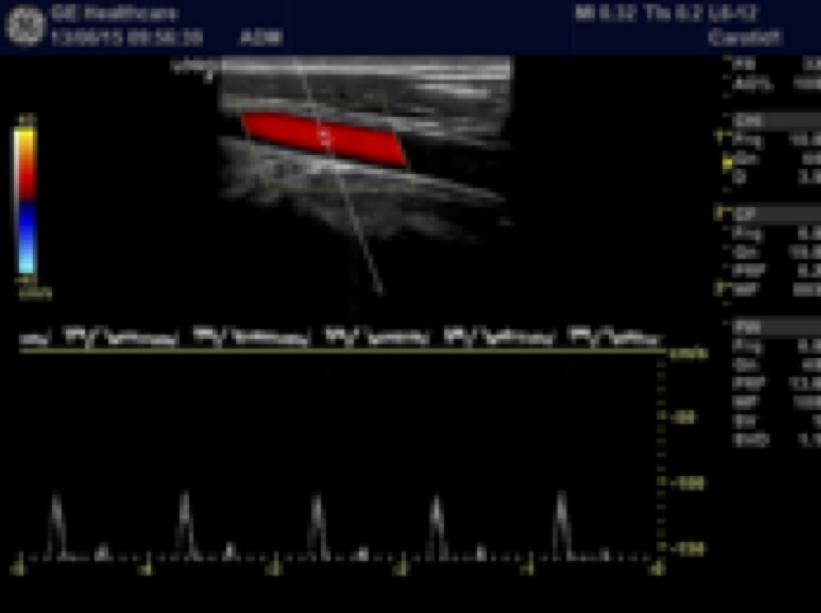

- Doppler Color

- Doppler Pulsado

- Paquete de medidas, anotaciones y cálculos para aplicaciones vasculares, urológicas, obstétricas, ginecológicas, cardiacas y de imagen general.